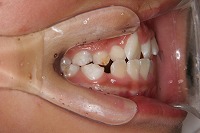

反対咬合を主訴に来院された、右側唇顎裂の10歳6ヵ月の女の子です。診断「右側唇顎口蓋裂で反対咬合を伴う」1期治療で反対咬合の解消と上顎の前歯の並びを修正しました。2期治療は抜歯をせず治療を行いました。